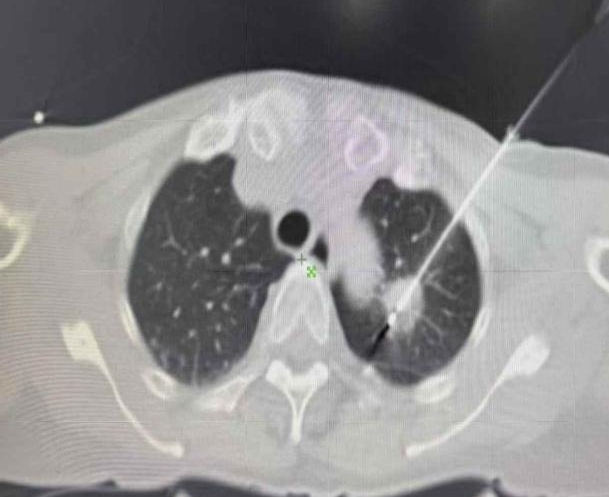

患者张某,64岁,体检发现左肺两处1.2cm结节,经多学科会诊评估后,胸外科团队决定采用射频消融术。手术在局麻下进行,通过CT精准定位,将射频电极针穿刺至结节部位进行消融。手术历时1小时,成功消除病变组织,患者术中无疼痛感,术后恢复良好。